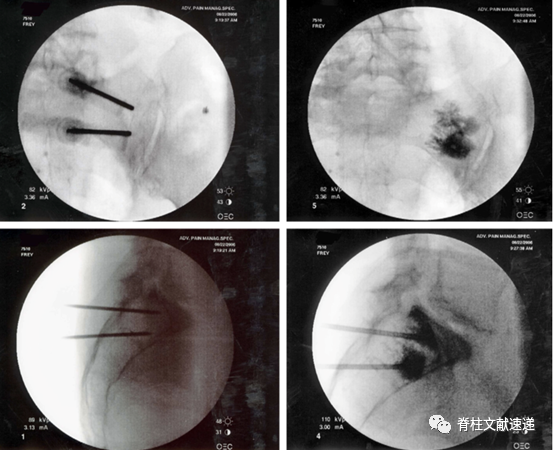

骶骨成形术手术操作:透视下将13G穿刺针置入骶后孔和骶髂关节中间的骶骨翼,与骶髂关节成45度,侧位上位于骶骨正中,一侧可以置入2-3根穿刺针,以保证骨水泥分布均匀,注入骨水泥时正位片上观察,避免骨水泥向内侧延伸,如下图所示。手术操作较胸腰椎椎体成形容易。